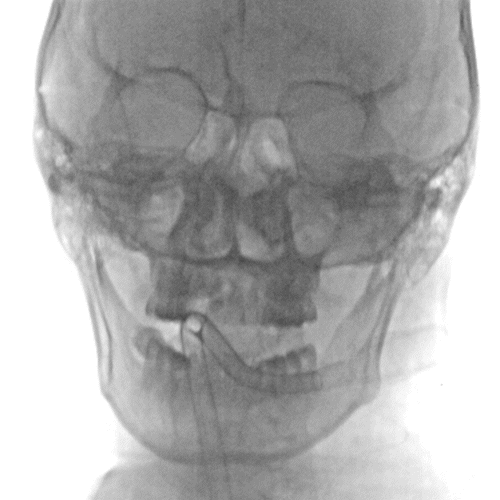

影像信息

左侧颈总动脉正侧位造影